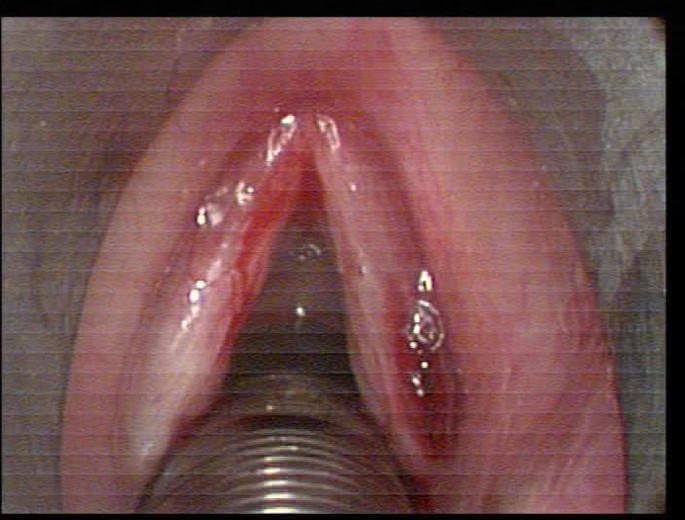

27/06/12 выполнено хирургическое лечение – эндоларингеальное удаление папиллом с применением «холодного» микроинструментария.

Рис. 2. Эндоларингеальная картина после операции